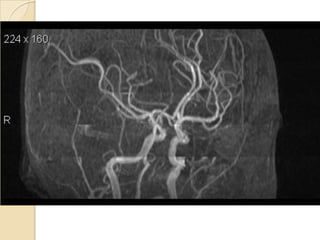

Arteries of the brain (lateral view) - MRA

1. Anterior cerebral artery

2. Anterior communicating artery

3. Basilar artery

4. branches (in insula) of middle cerebral artery

5. Cavernous portion of internal carotid artery

6. Cervical portion of internal carotid artery

7. Genu of middle cerebral artery

8. Intracranial (supraclinoid) internal carotid artery

9. Middle cerebral artery

10. Ophthalmic artery

11. Petrous portion of internal carotid artery

12. Posterior cerebral artery

13. Posterior cerebral artery in ambient cistern

14. posterior cerebral artery in interpeduncular

cistern

15. Posterior communicating artery

16. Posterior inf cerebellar artery.

17. Quadrigeminal portion of posterior cerebral

artery

18. Superior cerebellar artery

19. Vertebral artery